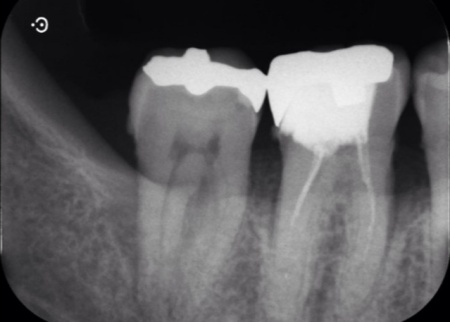

再生療法後は一定期間の経過観察を行い、歯ぐきの治癒状態や骨の回復状況を確認しています。

半年後のレントゲン検査では、失われていた骨の部分に新しい骨の形成が認められ、歯ぐきの腫れや出血も改善していました。

歯周組織の回復を確認したのち、右上奥歯の形を整え精密な型取りを行ったうえで、製作したe.maxセラミッククラウンを噛み合わせや見た目に配慮しながら装着しました。